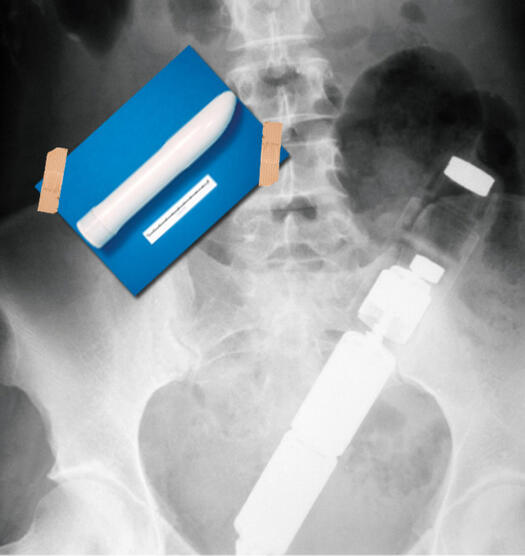

ЕКСПОНАТ 6

Вибратор в задника

Този атрубут е извлечен от отверстието на 35-годишен американец. Натататък спряхме да четем